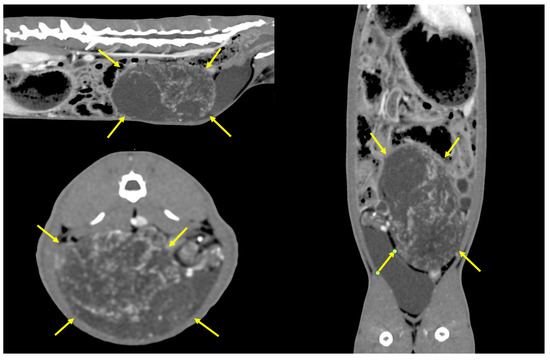

2. Clinical Case